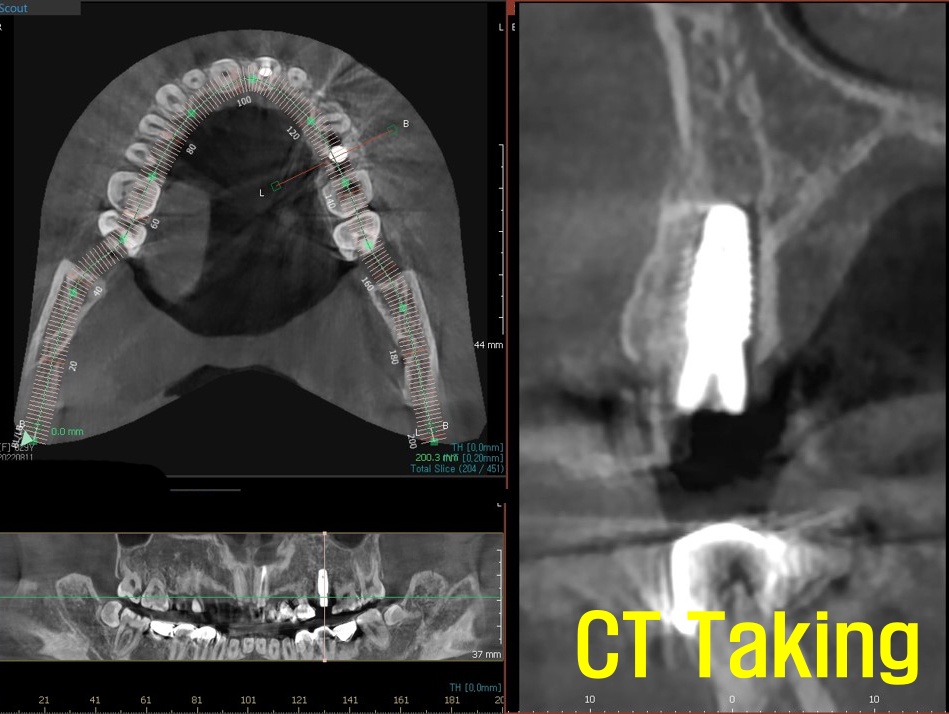

Implant 를 식립하기 위한 진단을 할 때는

CT를 찍습니다.

식립할 자리의 잇몸과 치조골의 상태,

골질과 골양을 진단하고,

주변 해부학 구조와의 관계를 확인합니다.

또한, 식립 시뮬레이션도 진행합니다.

발치 후 즉시 식립이 가능할 것으로

판단되면 상기 사진처럼 임플란트를 식립합니다.

잘 심겨졌는지

혹시 주변 구조물과의 관계는 어떤지

확인 을 위해 CT를 찍은 후 초기 고정도

괜찮다면 과정이 마무리됩니다.